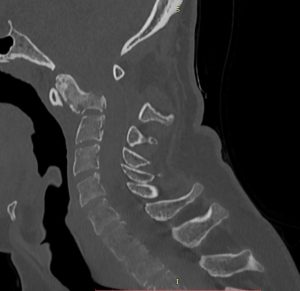

Ασθενής 20 ετών με εξεργασία στο σώμα του Α2 σπονδύλου (2ος σπόνδυλος της αυχενικής μοίρας της σπονδυλικής στήλης) με αποτελέσμα εξάρθρημα Α1-Α2 σπονδύλου και ατλαντοαξονική αστάθεια.

Η μετεγχειρητική πορεία της ασθενούς ήταν ανεπίπλεκτη και ο ασθενής εξήλθε την 3η μετεγχειρητική ημέρα. Η μετεγχειρητική αξονική τομογραφία και ακτινογραφία έδειξε ορθή θέση των μοσχευμάτων και πολύ ικανοποιητική θέση κεφαλής σε σχέση με την ΑΜΣΣ (βλ. εικόνες παρακάτω)